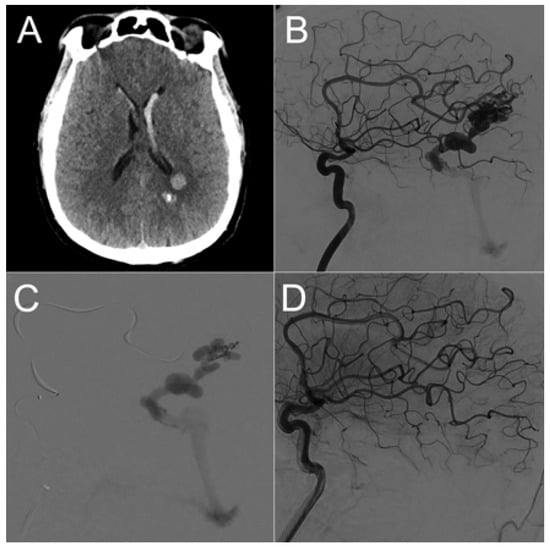

Six patients underwent endovascular management (Figure 3), two patients underwent surgical intervention, and two patients underwent a combined procedure involving embolization followed by surgery on the same day.

Figure 3.

Male patient in his 40s presenting with acute onset of headache. Emergency brain CT scan (A) revealed left parietal intraparenchymal hematoma and intraventricular hemorrhage. Digital subtraction angiography of the left internal carotid artery (ICA) lateral projection (B) showed an underlying left parietal bAVM. The two main arterial feeders originated from the pericallosal artery. Endovascular embolization was performed via distal microcatheterization of the feeders and ultra-selective angiography (C) followed by an injection of the embolic product (Onyx 18, Ev3 Neurovascular, Irvine, CA, USA). The final angiographic of the left ICA (D) shows complete bAVM exclusion.